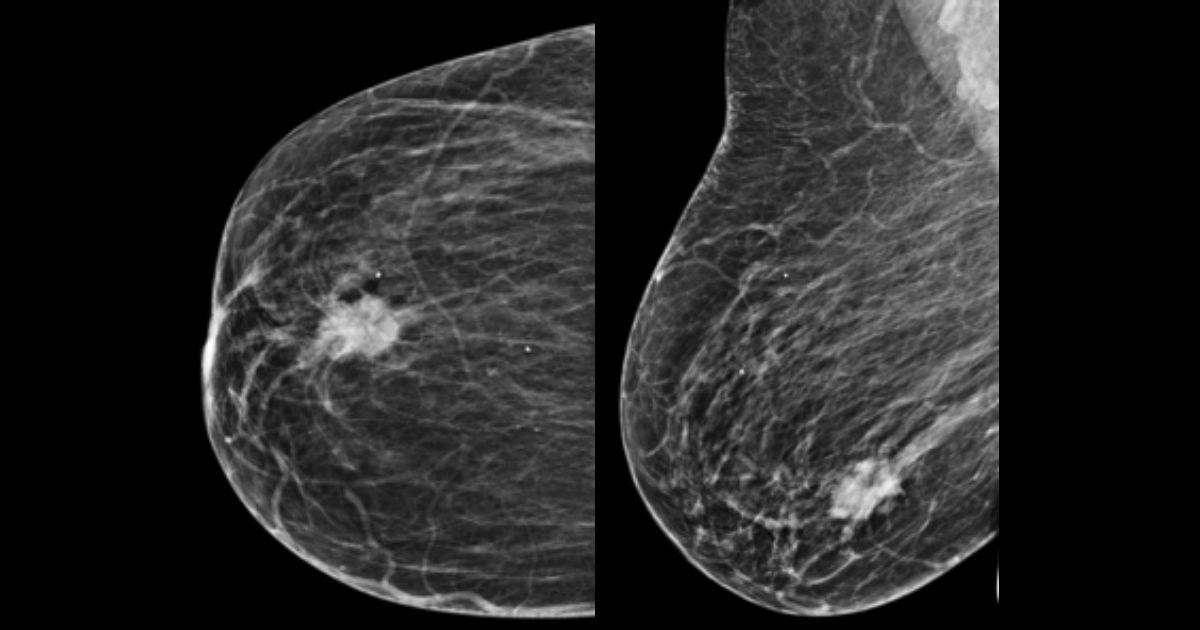

Campania "Îţi Oferim o Şansă pentru că Preţuim Viaţa", derulată de clinica Exmed din Alexandria, se află la cea de-a III-a ediţie şi se adresează femeilor cu vârsta de la 45 de ani în sus, obiectivul fiind prevenirea şi tratarea afecţiunilor mamare.

Practic, în perioada 25-28 octombrie, clinica efectuează gratuit mamografii, ecografii, analize de markeri tumorali sau direct puncţia pentru biopsie, fiecare pacientă primeşte rezultatele în aceeaşi zi şi are garanţia confidenţialităţii datelor personale. Campania a ajuns la a treia ediție, dar este prima dată când clinica are parteneriat cu Asociaţia pentru prevenţia şi lupta împotriva cancerului Amazonia şi Avon - şi colaboratori - Smart Medical.În urma selecţiei, femeile vor participa, pe 25 octombrie, la un curs de prevenţie susţinut de Victoria Asanache, trainer navigator de pacienţi, la sediul clinicii din str. Alexandru Ghica, în Alexandria. Pacientele vor fi îndrumate astfel încât să ştie să reacţioneze la un diagnostic sever, vor fi sfătuite şi ajutate să parcurgă etape în cazul depistării unei afecţiuni. Pe 28 octombrie, pacientele vor fi consultate de dr. Sebastian Grădinaru, medic primar chirug oncolog specialist în chirurgia sânului, iar în cazul în care sunt necesare alte investigaţii, organizatorii asigură gratuit analizele de sânge prin intermediul Clinicii Smart Medical.